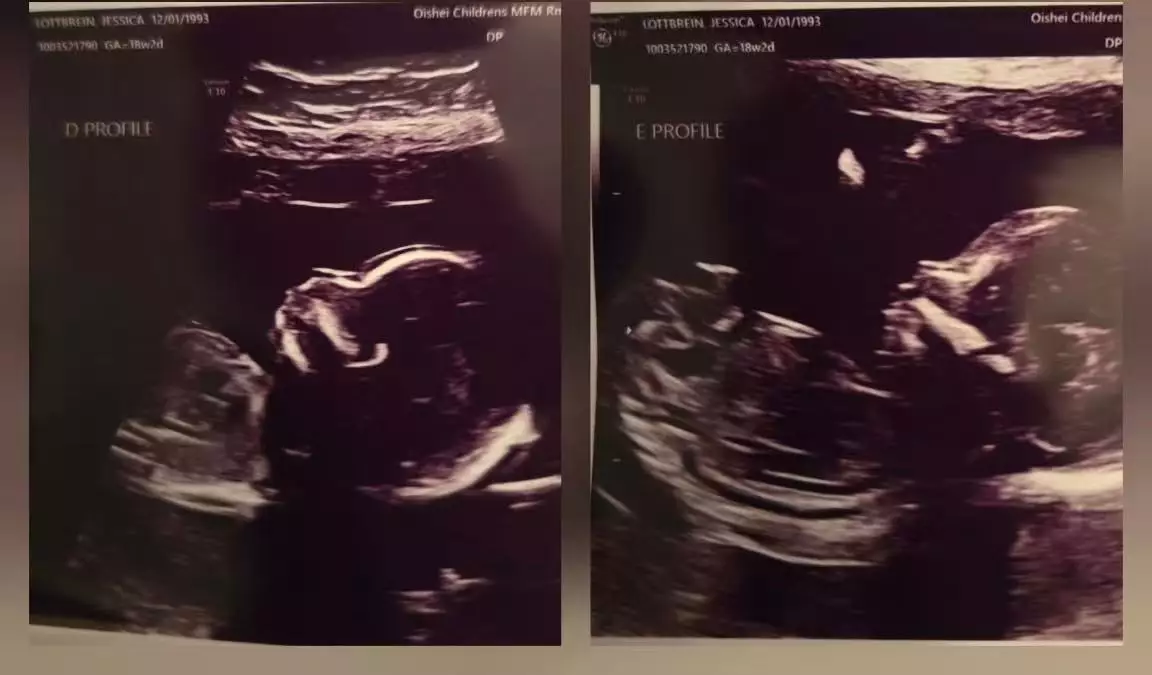

綜合外媒報導,美國紐約一對夫婦,傑西卡(Jessica)與約翰・洛特佈雷恩(John Lauterbrunn)迎來極為罕見的自然5胞胎,成為當地歷史上第二宗5胞胎誕生個案。據悉,夫婦得悉懷上5胞胎後,一度感到震驚與不安。傑西卡坦言,當下情緒幾近崩潰,直言「我非常驚慌,不知道該怎麼辦」,所幸丈夫即時安撫,並承諾會與她攜手面對未來挑戰,讓她逐漸穩定情緒。

戈利薩諾兒童醫院新生兒深切治療部(NICU)副主任瓦萊麗・埃爾伯森表示,5胞胎妊娠屬極為罕見且風險極高的情況,全球出現機率相當低,布法羅地區過往僅曾出現一次類似個案。由於屬高風險妊娠,母胎醫學中心聯同院內多個專科團隊提早展開周密部署,約30名醫護人員參與準備工作,涵蓋產科、新生兒深切治療、護理、藥房及呼吸治療等部門,確保生產過程安全順利。

28周早產順利分娩 5嬰兒被送NICU照護

醫生建議傑西卡於懷孕期間盡量維持日常作息,以穩定身心狀態。去年12月中旬,她因羊水破裂需緊急入院。至凌晨時分,在大批醫護團隊全力支援下順利分娩。5名嬰兒分別名為霍莉(Holly)、梅森(Mason)、史特凡(Stefan)、康納(Connor)及萊拉(Layla),於懷孕28周零5天時出生,屬早產兒,每名嬰兒出生時體重均不足3磅(約1.4公斤),出生後即被送往新生兒深切治療部接受密切照護。